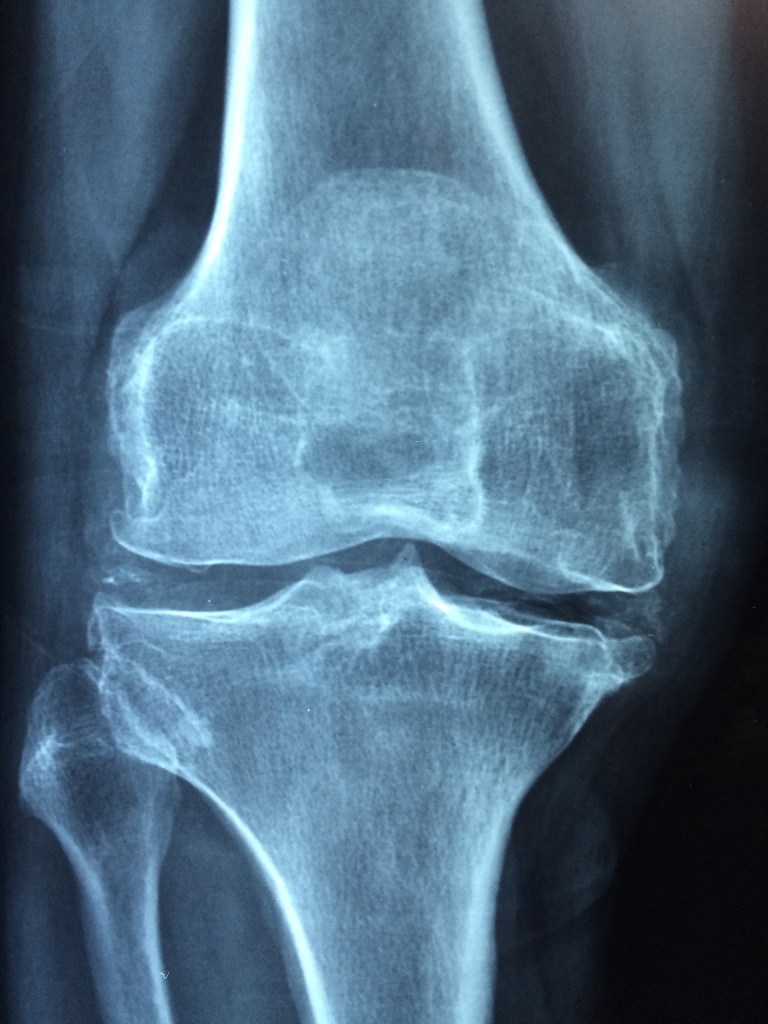

Osteoarthritis initially affects the smooth cartilage lining of the joint. This makes movement more difficult than usual, leading to pain and stiffness. Cartilage lining starts to roughen and thin out and tendons and ligaments need to work harder. This leads to swelling, and even the formation of bony spurs called osteophytes. In severe case this can lead to bone rubbing on bone which can change the shape of the joint and changing of normal bone positions. The most commonly affected joints are those in the spine, hands, knees and hips.